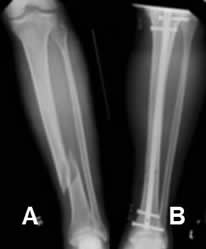

Fig 94. Clavo de Kuntcher.

A: Rx AP. Fractura espiroidea en la tibia distal.

B: Rx AP. Reducción anatómica y estabilización con clavo de Kuntcher.